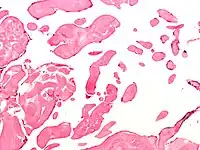

Low magnification micrograph of an excised aortic valve papillary fibroelastoma showing the characteristic avascular branching papillae, H&E stain | |

Papillary fibroelastoma are typically found and accurately diagnosed by imaging. The diagnosis is confirmed by pathology. Histologically, papillary fibroelastomas have branching avascular papillae, composed of collagen, that are covered by endothelium.